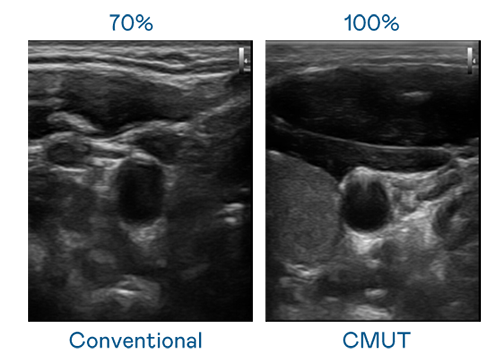

CMUT 技术是一种用电容式微机电元件来产生超音波讯号的技术。与传统 PZT 压电式技术相比,CMUT 频宽增加 30%,更宽频的超音波讯号让影像解析度大幅提升,是实现高影像品质医疗超音波扫描、促进精准医疗发展的关键技术。

大频宽带来超清晰影像

超音波影像的解析度高低,首先取决于探头能发出的讯号频宽。z6尊龙官方网站 CMUT 可提供高清晰的超音波讯号,提供高频宽、高灵敏度、影像纹理细节更高的超音波影像,协助医护人员缩短影像判读时间及利用精准的医疗影像进行诊断。